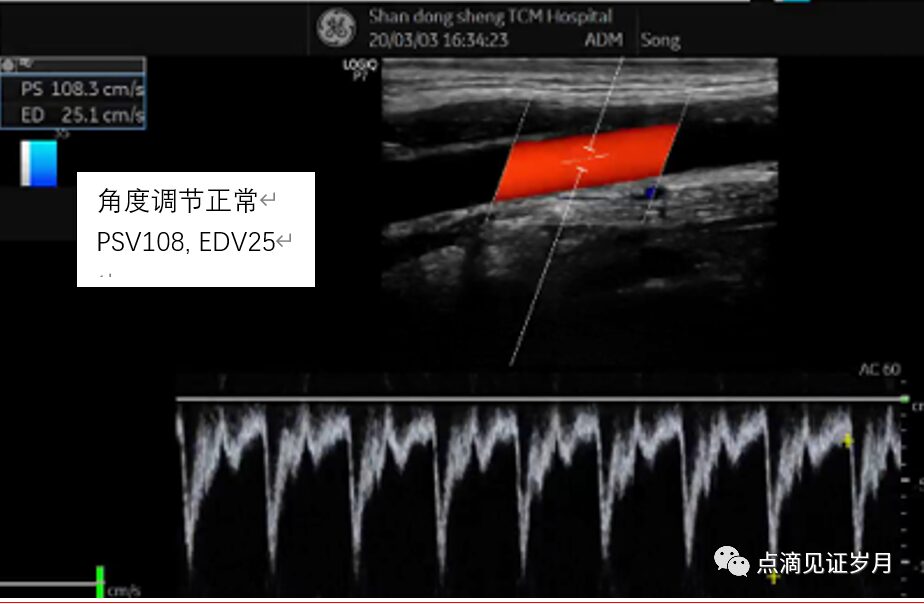

2.Angle Correction

This is a necessary step for quantitatively detecting blood flow speed. To accurately measure flow speed,the sampling should be done along the long axis of the vessel rather than the short or oblique axes, so the ratio of the length to the diameter of the measured blood vessel should be as large as possible.

Additionally, the long axis of the vessel should be as parallel to the sampling line as possible; generally, it should not exceed 60 degrees to keep the measurement error within an acceptable range.

In practice, adjusting the sampling line angle does not change the angle of the Doppler sound speed; its real effect is to measure the size of the angle between the sound speed and the blood flow angle being measured, which is calculated during post-processing to determine blood flow speed.

The sampling line is almost parallel to the blood vessel.

The variation of the sampling angle synchronously affects the values of PSV and EDV, so the sizes of S/D, PI, and RI are unaffected.